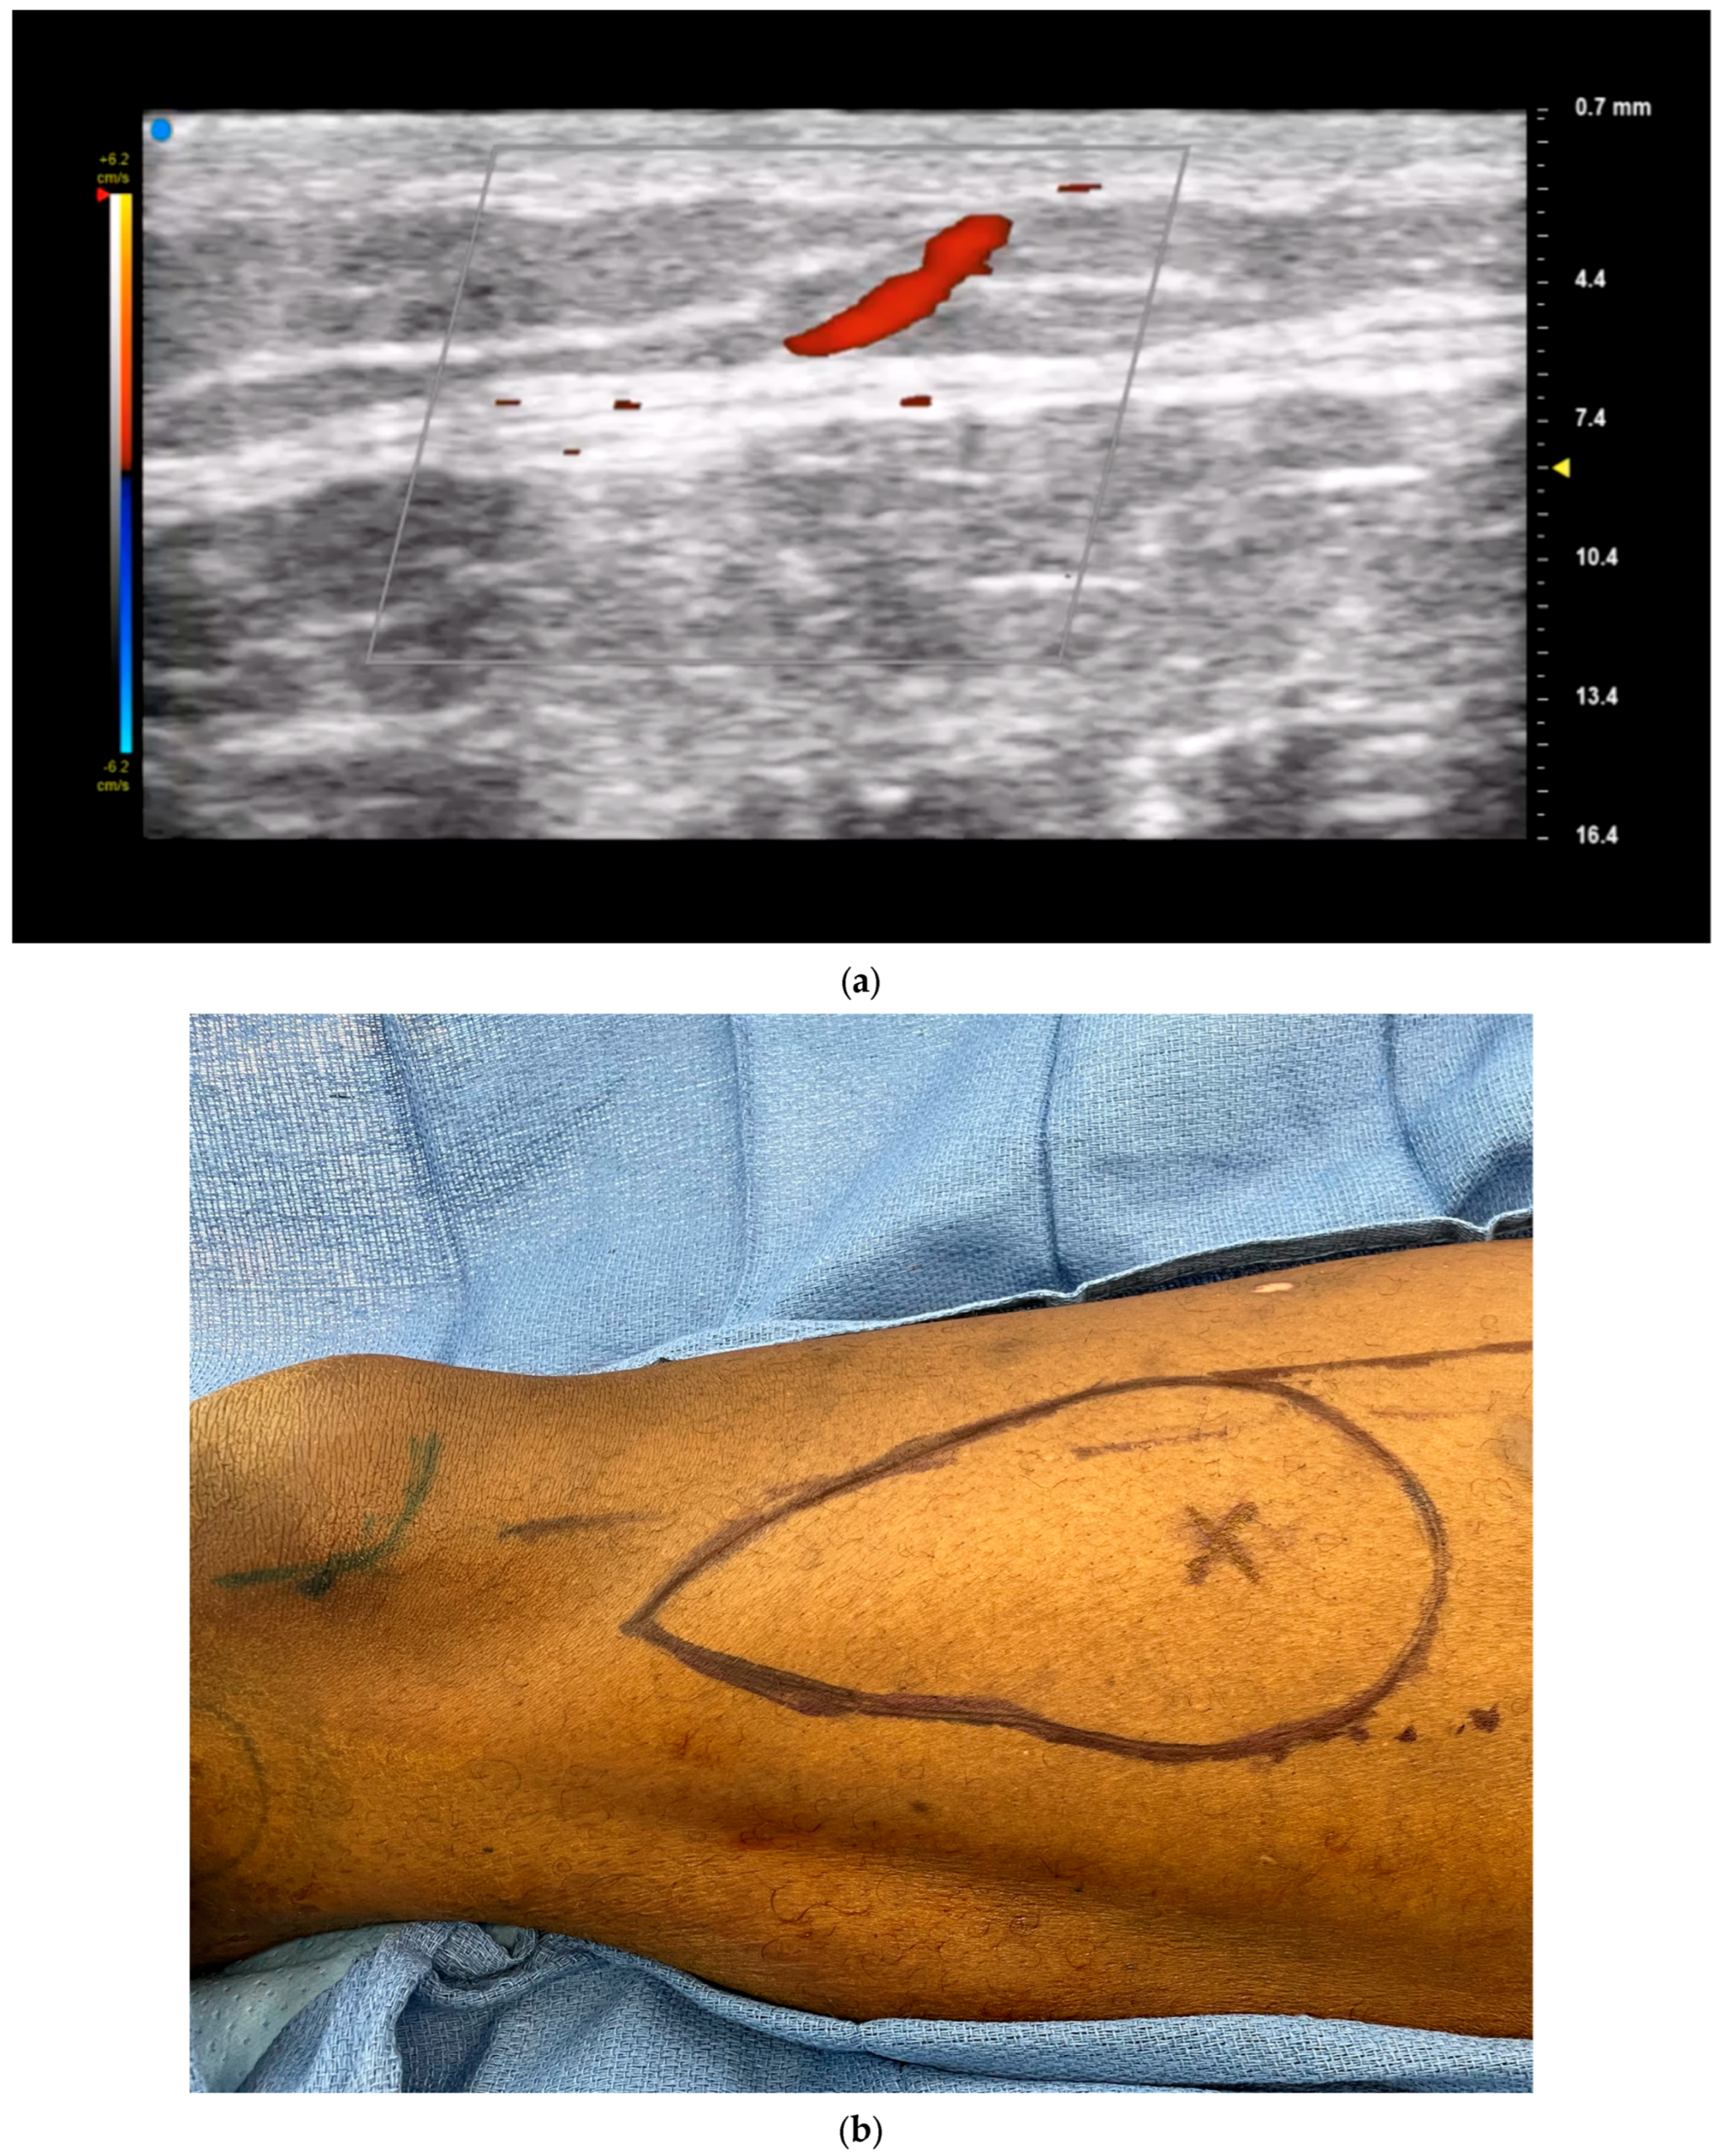

3.1. Perforator Flap Planning and Design

- Kehrer, A.; Sachanadani, N.S.; da Silva, N.P.B.; Lonic, D.; Heidekrueger, P.; Taeger, C.D.; Klein, S.; Jung, E.M.; Prantl, L.; Hong, J.-P. Step-by-step guide to ultrasound-based design of alt flaps by the microsurgeon—Basic and advanced applications and device settings. J. Plast. Reconstr. Aesthetic Surg. 2020, 73, 1081–1090. [Google Scholar] [CrossRef] [PubMed]

- Visconti, G.; Bianchi, A.; Hayashi, A.; Salgarello, M. Designing an Anterolateral Thigh Flap Using Ultrasound. J. Reconstr. Microsurg. 2021, 38, 206–216. [Google Scholar] [CrossRef] [PubMed]